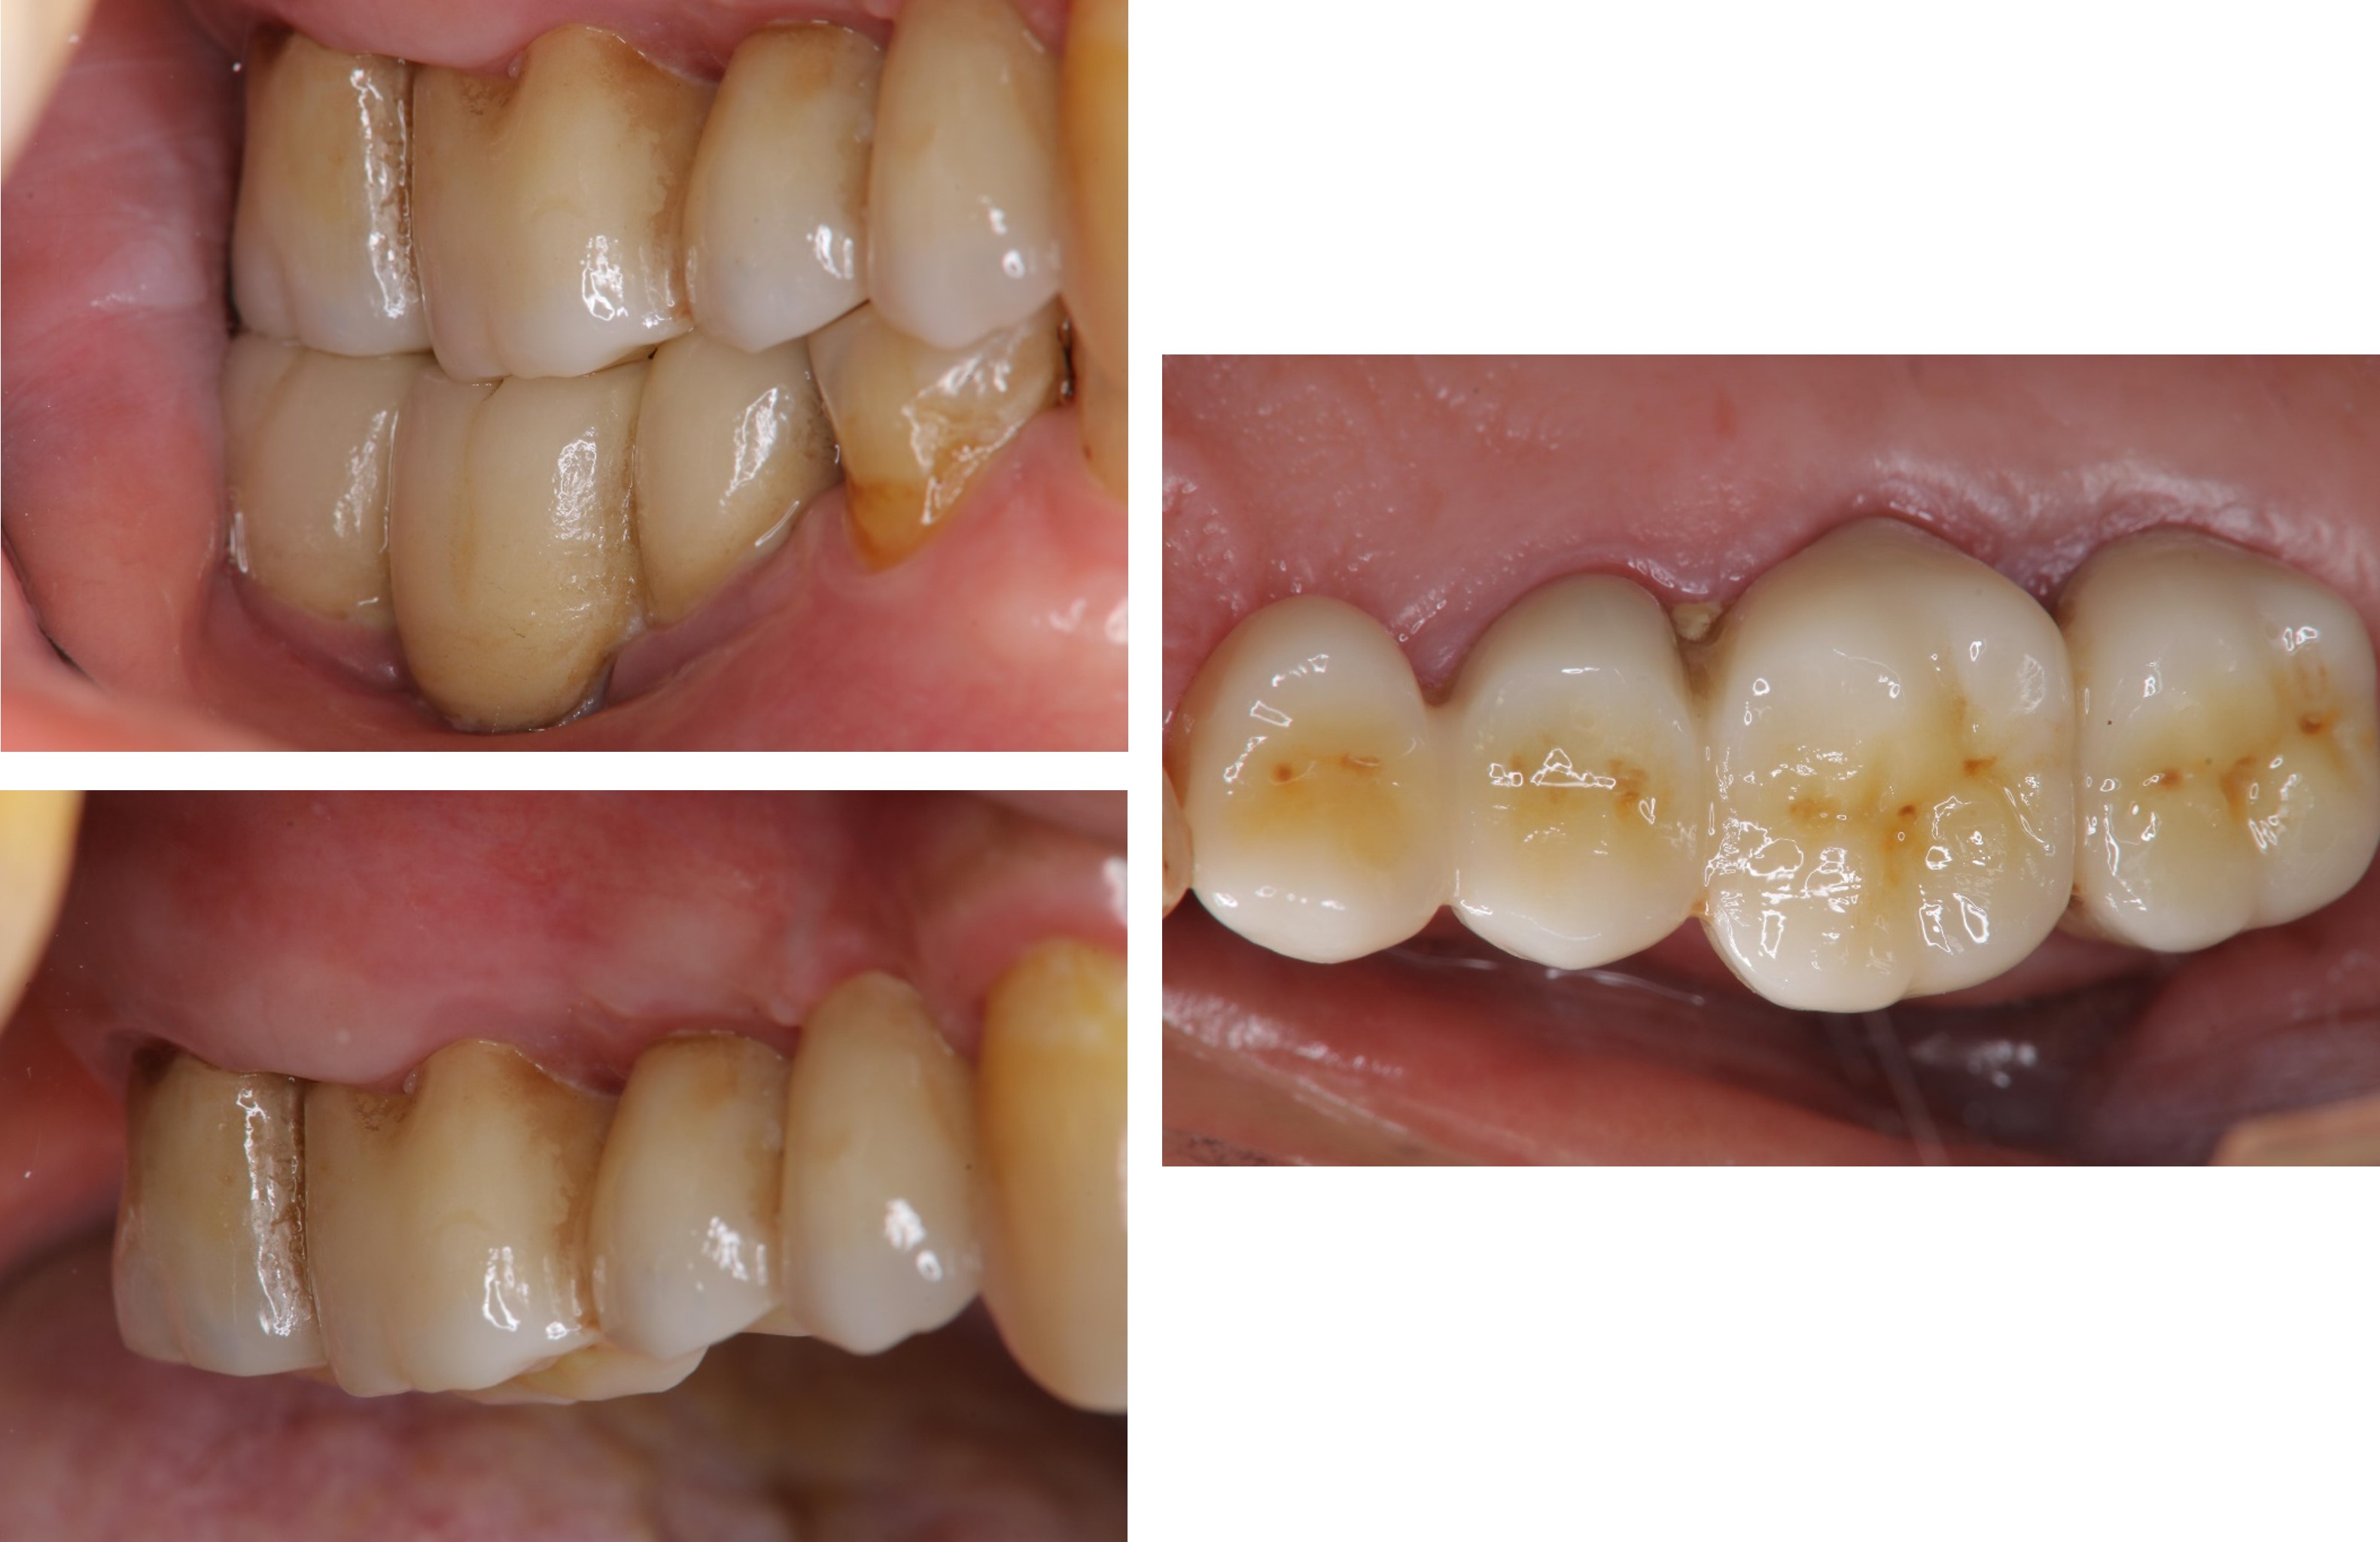

治療後,咬合良好

治療後,密合度良好

術前、術後比較